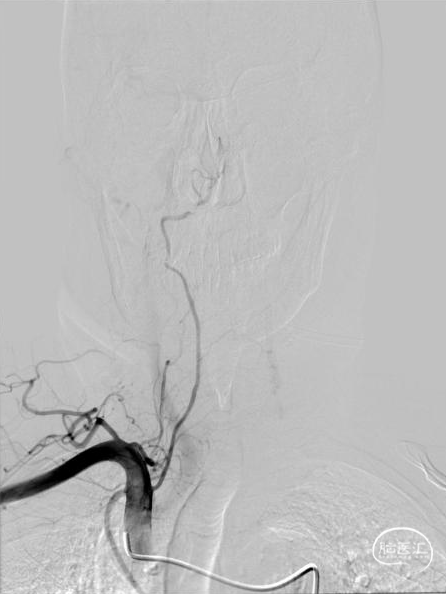

➢术后即刻影像

术中造影证实右椎纤细、右椎V4段可见微弱血流入基底动脉、左椎动脉开口闭塞、颈升动脉通过侧支循环向左椎V3供血并逆流至V1中段、左椎V4轻度狭窄;

对于该类病变我们的最优选择就是处理左侧椎动脉起始部。针对路径迂曲,其实当我们的微导丝通过病变到达左椎V3段时可明显看见血管拉直,迂曲的管径问题迎刃而解;

为减少血栓逃逸事件的发生及对椎动脉血管的刺激,我们选取了预留中间管+Syphonet®取栓支架作SWIM取栓准备。这款支架全程显影,且头端带网篮,对球囊扩张过程中的逃逸血栓有抓捕能力,且抗折性强,迂曲血管内能保持完整管腔,内置的支架输送导丝头端柔软可避免血管损伤,在该病例中发挥了保护伞的作用。